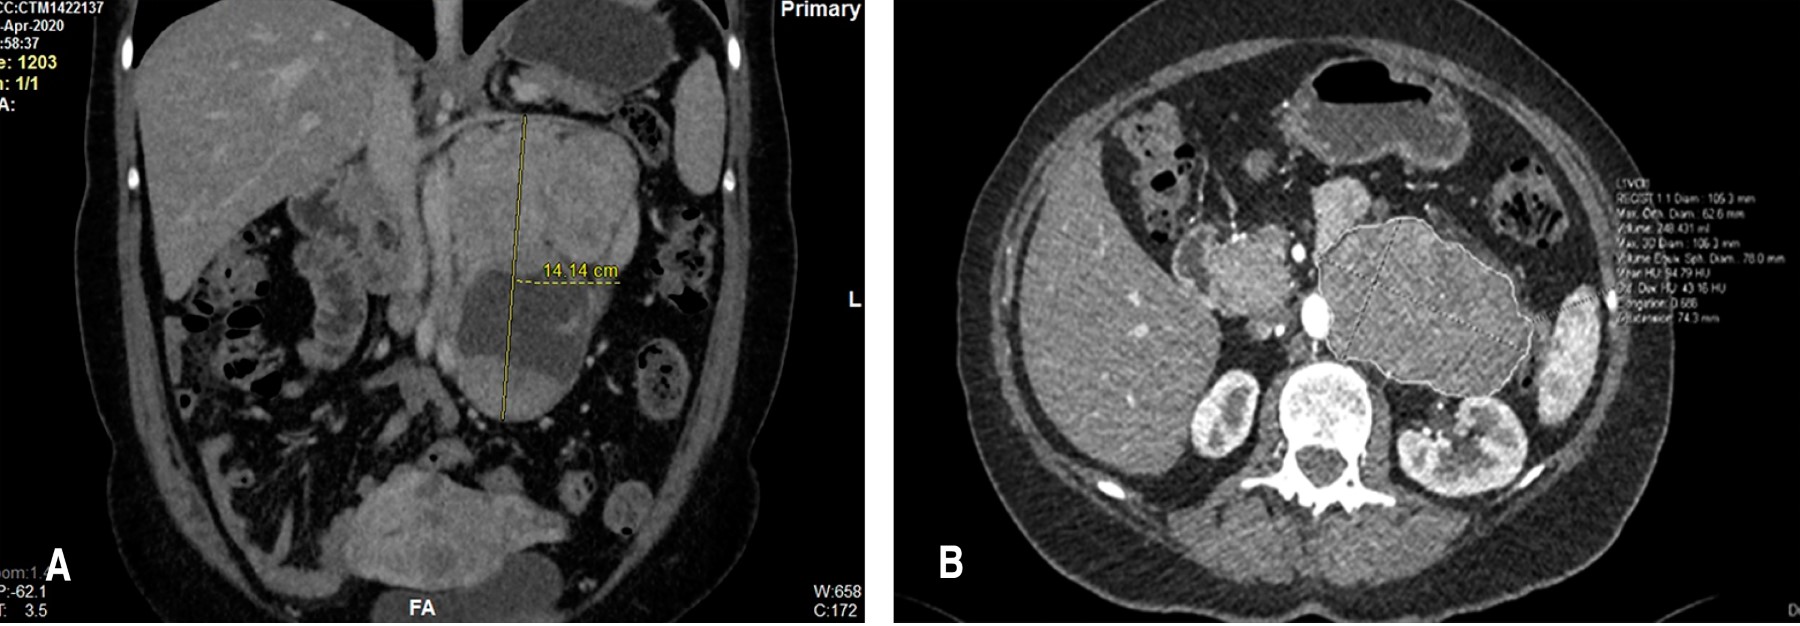

Como planeación quirúrgica, se solicitó angiotomografía axial computarizada (Figura 1) donde se reportaron vasos nutricios de las lesiones lateroaórticas, dependientes de arteria lumbar izquierda a nivel de L2, así como ramas del tercio medio de la arteria mesentérica inferior, con desplazamiento anterior de arteria ovárica izquierda. Lesión lateroaórtica inferior con rama dependiente del tercio proximal de la arteria iliaca común izquierda. Lesiones a nivel de la pelvis con ramas dependientes de arteria iliaca interna derecha.

Después de la discusión con un equipo multidisciplinario, se decidió resolución quirúrgica. Se realizó pielografía ascendente y colocación de catéter doble J en uréter izquierdo para facilitar su identificación. Se realizó laparotomía exploradora, se movilizó el colon izquierdo con maniobra de Mattox para lograr acceder al retroperitoneo. Se realizó disección, encontrando tumor aproximadamente 16 × 7 cm, lobulado, de consistencia ahulada (Figura 2). Se encontró en relación estrecha con aorta y arteria iliaca izquierda en su cara medial, región lateral en relación con uréter izquierdo, el cual se identificó y lateralizó (Figura 3). Polo superior del tumor en relación con arteria ovárica, la cual se visualiza desplazada. Se liga y corta. Se identifica dependencia del tumor del músculo psoas, el cual se separa con bisturí armónico. Se encuentra vaso tributario proveniente de arteria lumbar y arteria mesentérica inferior, se realiza control vascular y se extrae tumor.